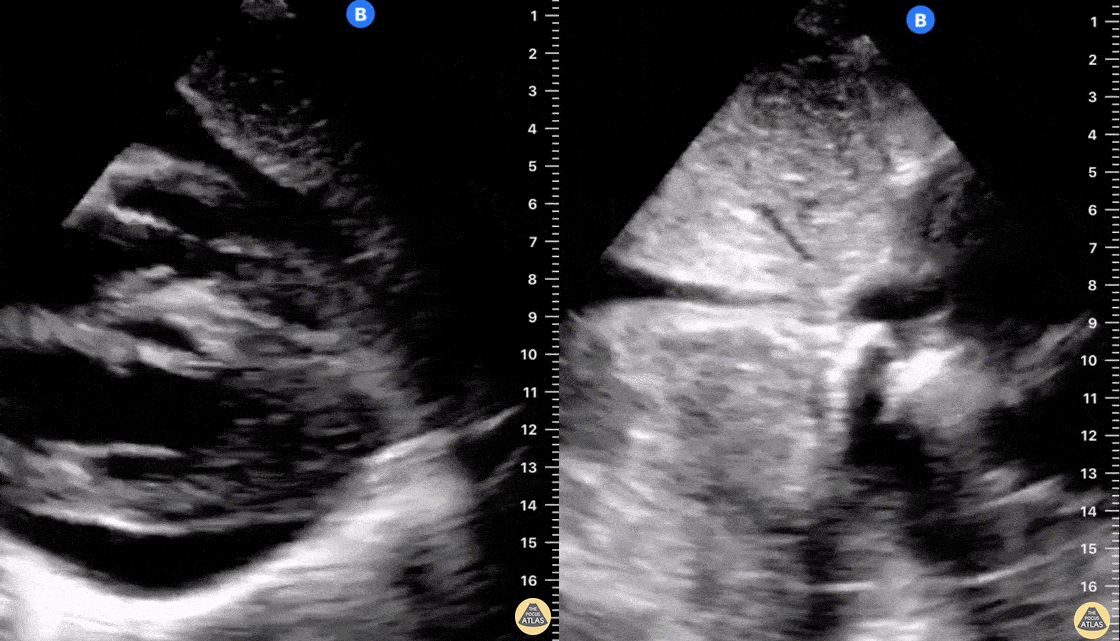

Seen here is a subxiphoid view of a moderate sized, free-flowing pericardial effusion. There is >50% collapsible IVC which makes tamponade less likely in the absence of clinical signs of hemodynamic deterioration (i.e. normal blood pressure, mild tachycardia and pulsus paradoxus <10 mmHg). Plethora of the IVC in pericardial effusion is associated with elevated right heart filling pressures and is more sensitive though less specific for tamponade than right heart chamber collapse or jugular venous distention. Plethora of the IVC also has greater sensitivity than does elevated jugular venous distention on physical examination (97% versus 61%). Reference: Ronald Himelman, Barbara Kircher, Don Rockey, Nelson Schiller. Inferior vena cava plethora with blunted respiratory response: A sensitive echocardiography sign of cardiac tamponade. JACC. 1988; 12:1470-1477. Shahad Al Chalaby, MD (PGY3) @shahad_Chalaby Alameda Health System Internal Medicine Residency Program Oakland, CA